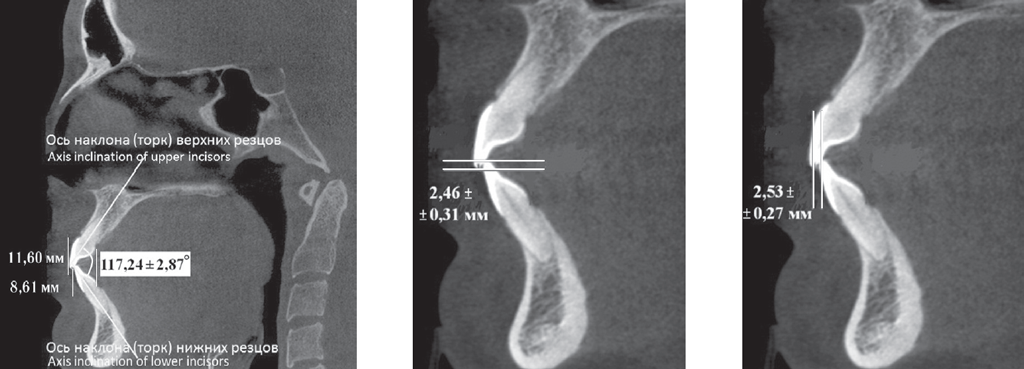

У людей 1-й подгруппы, для которых было характерно протрузионное положение резцов, межрезцовый угол составил 117,24 ± 2,85°. При этом торковые значения верхних резцов по отношению к окклюзионной плоскости составили 12,24 ± 2,48° (рис. 2).

Рис. 2. Физиологическая протрузия резцов на томограммах

Fig. 2. Physiological protrusion of incisors on tomograms

У людей 1-й подгруппы, для которых было характерно протрузионное положение резцов, межрезцовый угол составил 117,24 ± 2,85°, при этом торковые значения верхних резцов по отношению к окклюзионной плоскости — 12,24 ± 2,48° (рис. 4).

Рис. 4. Патологическая ретрузия (а) и патологическая протрузия (b)

Fig. 4. Pathological retrusion (a) and pathological protrusion (b)

У пациентов с ретрузией резцов отмечалось увеличение межрезцового угла и уменьшение торковых значений резцов, так же как и при физиологической ретрузии. Однако величина перекрытия существенно отличалась от аналогичных показателей, полученных у пациентов I группы. При этом наблюдалось несоответствие размеров вертикального и сагиттального перекрытия.